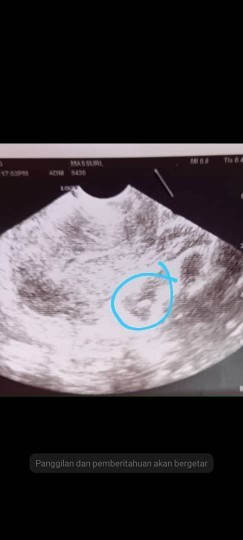

Dh lewat period 13 hari..then sakit perut yg x tahan buat upt neg dn dgitalnya punya neg..then arini g scan doc kata dh ad kantung tp xde jantung,agak2 sy pregant ke??risau buat upt neg walaupun dh ad kantung bby??doc suruh dtg scan lg 2 minggu